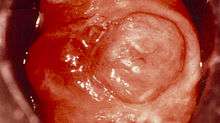

_cervix_(5).jpg)

DES (diethylstilbestrol)

DES (diethylstilbestrol) is a drug that mimics estrogen, a female hormone. From 1938 until 1971 doctors prescribed this drug to help some pregnant women who had had miscarriages or premature deliveries on the theory that miscarriages and premature births occurred because some pregnant women did not produce enough estrogen naturally to sustain the pregnancy for full term . An estimated 5-10 million pregnant women and the children born during this period were exposed to DES. Currently, DES is known to increase the risk of breast cancer, and cause a variety of birth-related adverse outcomes exposed female offsprings such as spontaneous abortion, second-trimester pregnancy loss, preterm delivery, stillbirth, neonatal death, sub/infertility and cancer of reproductive tissues . DES is an important developmental toxicant which links the fetal basis of adult disease.[13]